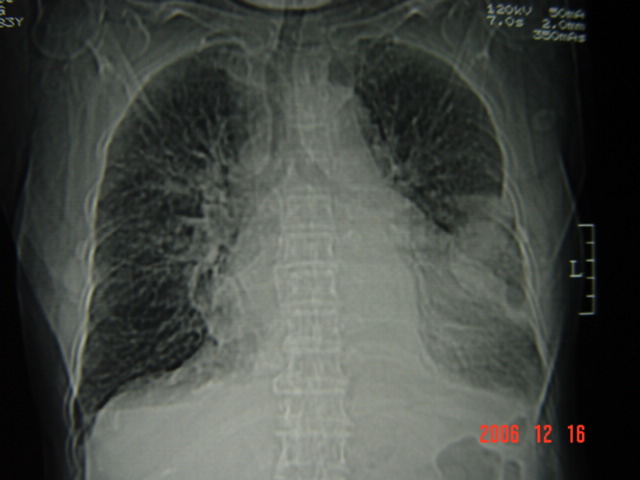

标题: CT5663:女、83岁,轻微咳嗽、左下胸痛。 [打印本页]

标题: CT5663:女、83岁,轻微咳嗽、左下胸痛。

左第八肋腋侧呈膨胀性骨质破坏,内侧见软组织密度肿块。左肺舌段呈楔形实变,基底近胸壁,尖端向肺门。双侧胸壁后缘见新月形水样密度区。

考虑:1、左第8肋骨转移瘤;

2、左肺舌叶肺栓塞可能性大;

3、双侧中量胸腔积液。